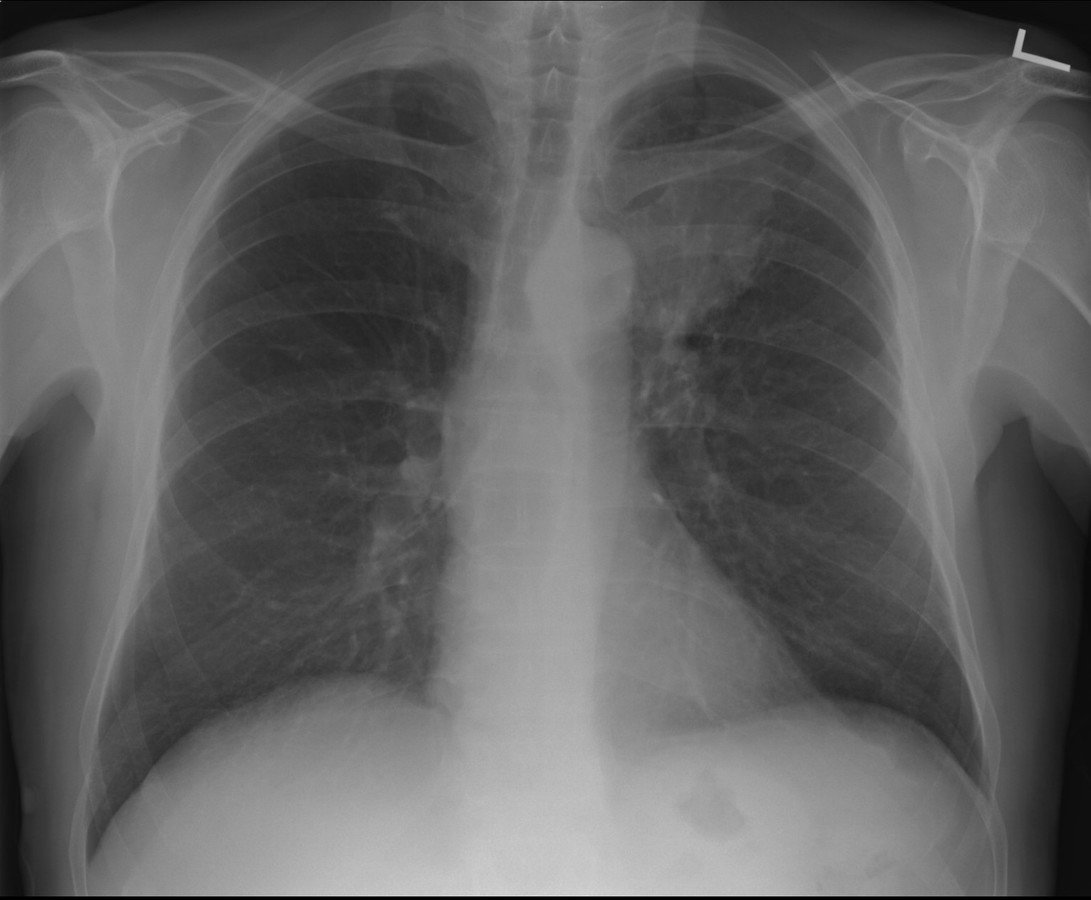

Radiography

(X-Rays)

- Uses ionizing radiation

How does it work?

- X-ray beam passed through the body

- Portion of the beam is scattered or absorbed by bones, organs, etc.

- Remaining pattern is transmitted to a detector for further processing as a picture

- Useful for detecting bone problems, infection, and tumors